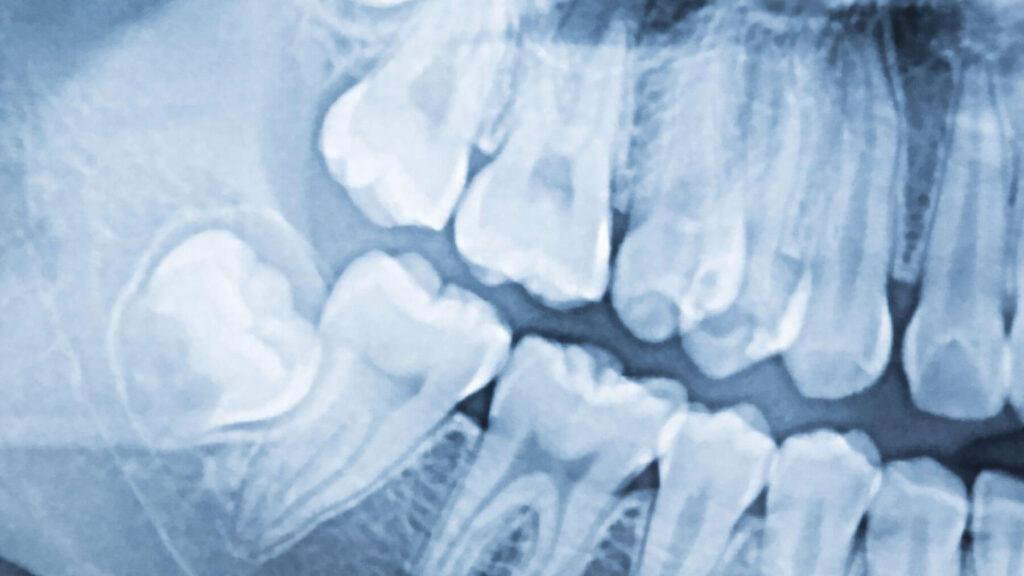

- Impaction: The most significant factor is whether the wisdom tooth is impacted. A fully impacted tooth (one that’s completely encased in bone) will take longer to remove than a partially erupted or non-impacted tooth. The depth and angle of impaction are crucial here.

- Angle of the Tooth: If the wisdom tooth is growing in at an unusual angle, such as horizontally or angled towards another tooth, it can complicate the removal and extend the wisdom teeth extraction duration.

- Root Structure: Wisdom teeth can have complex root systems. Curved, long, or tangled roots can make the extraction more challenging and add to the time it takes to remove wisdom teeth.